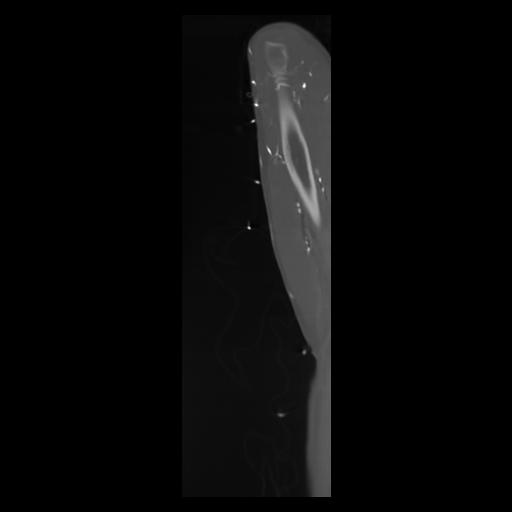

30 CUERPO,CE,Sagittal,3.000,CUERPO,Sagittal,